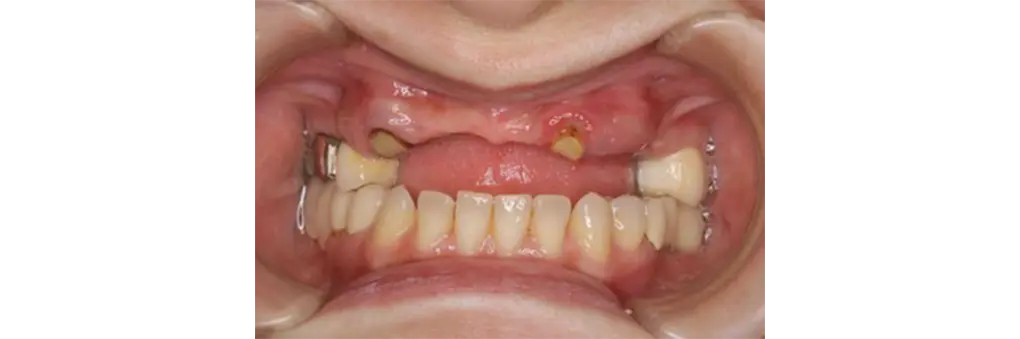

【症例3】インプラントオーバーデンチャー(50代女性)

| 主訴・背景 | 金属のバネのないしっかり咬める義歯にして欲しい |

|---|---|

| 診断・治療前の状態 | クラスプの金属が見えて審美的でない。義歯の動揺有り |

| 治療方針・計画 | 固定式のブリッジをご希望でしたが費用がかさむためインプラントオーバーデンチャーを選択。 残根歯にマグネット維持装置、インプラントを埋入してロケーター維持装置によるインプラントオーバーデンチャーの製作。 |

| 手術・処置内容 | ⚫︎ 治療部位13,21,25 インプラント3本 ⚫︎ ストローマン社 BLT TL ⚫︎ ロケーター維持装置によるオーバーデンチャー |

| 治療期間・回数 | 治療期間3カ月/治療回数5回 |

| 費用・料金(自費診療の場合) | 1,290,000円 |

| リスク・注意点・術後ケア | 義歯破損、インプラント周囲炎、定期検診 |

| 治療後の状態・経過写真 | 金属のバネも見えず、よく咬める。 術後3年経過して3カ月毎の定期検診で来院され、清掃状態も良好。 |

| まとめ・院からのコメント | きちんと3カ月に一度の定期検診に来られ、口腔清掃状態も良好 |